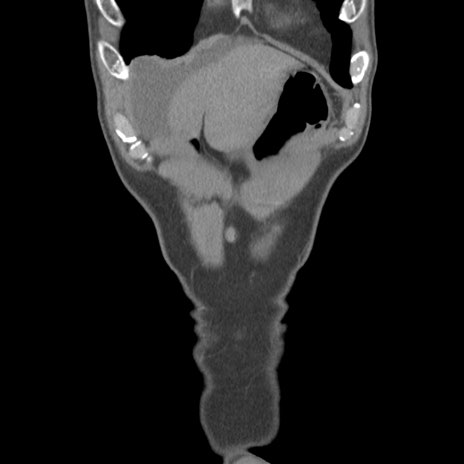

症例56 CT(冠状断像)

横断像